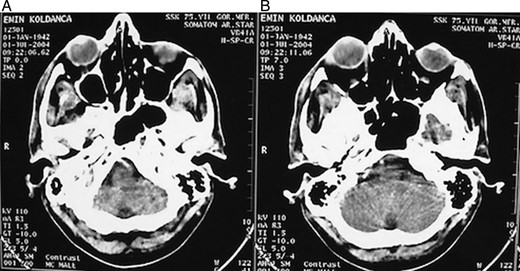

A 62-year-old male patient referred to our clinic due to painless exophthalmia of his right eye for the last 2 years. On neurological examination of the patient, there was no abnormality except for the up-gaze restriction and severe exophthalmia. Computerized tomography revealed an intraorbital mass in the right eye. A well-defined 2.5-cm isodense mass was located on the right lacrimal gland. The mass was contrasted homogenously (Fig. 1a and b). Cranial magnetic resonance imaging (MRI) revealed an isointense mass on the superolateral part of right orbita in the coronal intersections and it was contrasted homogenously (Fig. 2a and b). The existing score of our patient according to Rose and Wright was +8 points. Combined orbitofrontal craniotomy was performed through a transcranial approach. The well-defined, soft, white, 2.5-cm mass was removed completely. Exophthalmoses disappeared after the surgery (Fig. 3a and b). Histological examination of the surgical specimen covered the epithelial and stromal components that formed the glandular structures. Keratinized plugs were seen in some glandular lumens. Cartilaginous differentiation of stroma was found (Fig. 4a–d). Based on these findings, the tumor was diagnosed as pleomorphic adenoma. There was no recurrence after 8-year clinical follow-up.

(A and B) Computerized tomography revealed a homogenously contrasted intraorbital mass in the right eye.